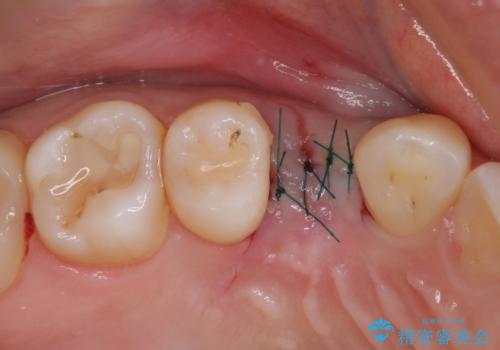

- 外科手術のため、術後に痛みや腫れ、違和感を伴います

- メンテナンスを怠ったり喫煙により、お口の中に大きな悪影響を及ぼすインプラント周囲炎等にかかる可能性があります